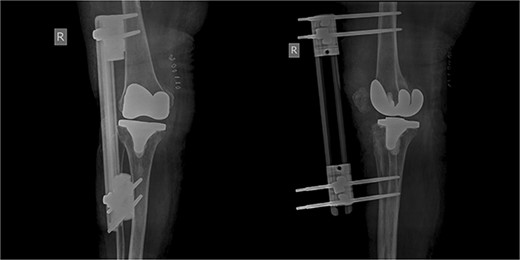

The patient was reoperated, where a more extensive release of the hamstrings was performed, obtaining full extension. The knee was stabilized using a lateral external fixator (Fig. 5). Muscle biopsies were obtained, indicating signs of chronic inflammation. Full weight bearing, using a walker, was permitted from the first postoperative day without substantial complaints.

The external fixator was removed after 6 weeks (Fig. 6), and physical therapy was initiated. The patient’s postoperative course was uncomplicated. One week upon removal, 0°–80° of flexion was achieved through everyday kinesiotherapy. On her last visit, 1 year postoperatively, the patient was ambulatory, with knee ROM of 0°–100° (Fig. 7). No further abnormal neuromuscular signs were observed.